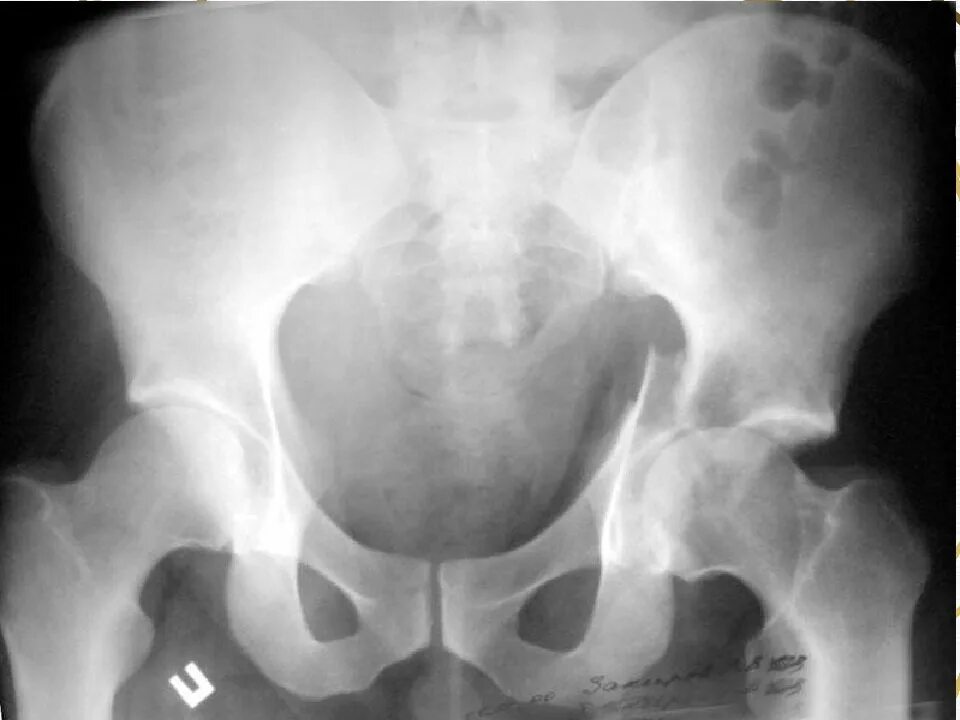

Перелом тазобедренной впадины